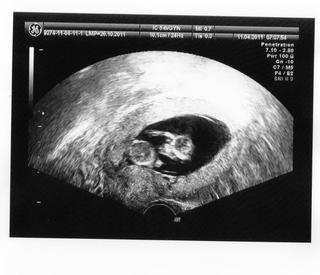

Ahojte 🙂 Tak sme doma 🙂 NT screening dopadol výborne, NT meranie 1mm 😉 Zajtra ideme do poradne tak budeme vedieť ostatné výsledky krvi atď. Podľa UTZ zodpovedáme 12tt+0, malá piškótka krásne rastie máme už 53mm a všetko je v úplnom poriadku. Hematóm zmizol takže sme čistý 😉 Maličké bolo dosť lenivé, nechcelo sa fotiť, ale tak nakoniec aby sa nepovedalo tak nám ukázal ako sa vie poškrabať rúčkou po hlavičke viď foto 😉 😉 😉